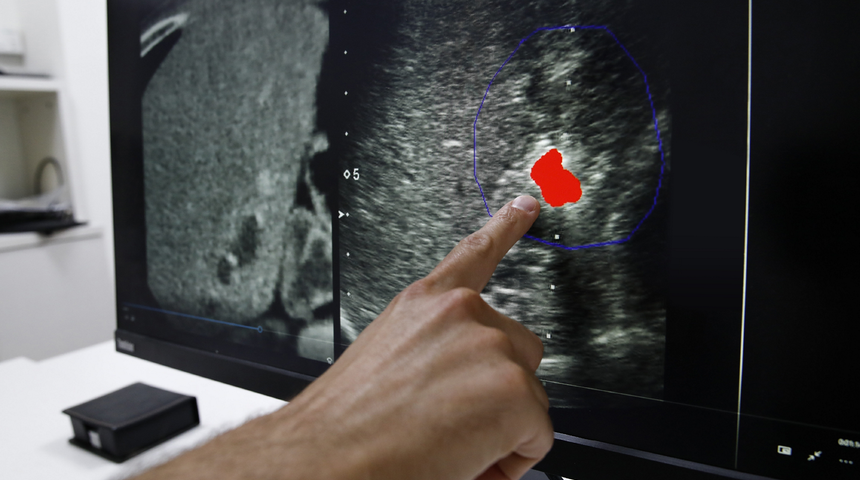

Tıbbi görüntüleme şirketi TechsoMed, onlarca yıllık tıbbi yöntemleri gücünü algoritmadan alan yenilikçi teknoloji ile birleştirerek doktorların belirli tümörleri tedavi etme biçiminde devrim yaratıyor.

Lenovo ve TechsoMed, iş birlikleri çerçevesinde az bilinen bir kanser tedavisi olan termal ablasyonu yaygın hale getirmeyi hedefliyorlar. Termal ablasyon, çapı üç santimetreden küçük olan erken aşama tümörlere yoğun ısı uygulanması yoluyla çalışıyor. Kemoterapi ile geleneksel tümörün çıkarılması hastalar üzerinde hem fiziksel hem de finansal yönden çok büyük bir etki yaratıyor. Bu standart tedaviler, on binlerce dolara mal oluyor ve ciddi riskler ve komplikasyonlar içeriyor. Geleneksel tedavi yöntemleri aynı zamanda günler veya haftalar süren bir iyileşme süreci de gerektiriyor. Diğer yandan yeni teknolojilerden faydalanan termal ablasyon tedavisi, beş dakikadan kısa sürüyor ve minimal bir cerrahi müdahale gerektiriyor.Termal ablasyon ayrıca sadece lokal anestezi kullanılarak uygulanıyor. Yöntem daha az potansiyel komplikasyon ile sonuçlanıyor ve çok daha kısa iyileşme süreleri gerektiriyor. Ayrıca, maliyeti de alternatifinin onda birine ulaşan oranda daha düşük.

TechsoMed, BioTrace'in gerçek zamanlı görüntüleme yeteneklerine güç katan yapay zekâ algoritmalarını, çok sayıda karmaşık görevi aynı anda yerine getirmek için gerekli merkezi işlemci, grafik işlemci ve bellek kapasitesine sahip olan Lenovo ThinkStation P920'ler üzerinde geliştirdi. ThinkStation'ın işini içeride serin ve dışarıda sessiz bir biçimde yapabilmesi, ablasyon işlemleri sırasında çok büyük önem taşıyor.